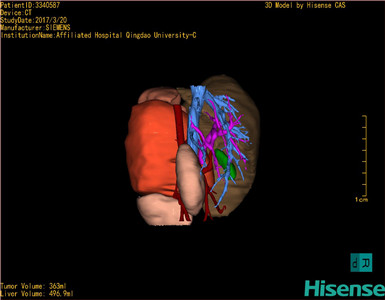

术前三维重建及手术方案设计:

将0.625mm双源薄层CT资料的静脉期和动脉期Dicom格式文件导入海信CAS系统。

通过调节窗宽窗位调整CT序号,对肿瘤,肝实质,胆囊,下腔静脉,肿瘤,肝动脉、门静脉及肝静脉等进行三维重建;系统自动计算肿瘤体积和肝脏体积。

模拟手术操作,自动计算切除肿瘤体积。肝脏体积为496.9ml,肾上腺肿瘤体积363ml,术前规划手术方案,进行手术。

麻醉成功后,置患儿平卧位,2.5%碘伏消毒手术区皮肤,铺无菌巾单。取左上腹横切口长约16cm,切开皮肤、皮下、肌层和腹膜。剪开后腹膜。探查见:左肾上腺区有一约16×10×10cm肿物,质地不均匀,边界清楚,包膜完整,与肾血管、下腔静脉、脾脏及左肾关系密切。从肿瘤外缘仔细分离肿瘤,分离出左肾动静脉以及下腔静脉,将肿瘤完整剥除。蒸馏水冲洗腹腔以及腹膜后。检查无活动性出血,清点纱布器械无误,放置腹膜后引流管一根,依次缝合腹壁各层。手术顺利,麻醉满意,出血10ml,输血0.5单位,术后病人安送麻醉恢复室,苏醒后回病房,术后标本送病理,结果回示:(左侧)肾上腺皮质源性肿瘤。手术时手术者可开启Hisense CAS系统手势控制功能,对肿瘤的解剖结构进行实时、全方观察、评估,起到术中导航作用。

术前三维重建:

重建图片